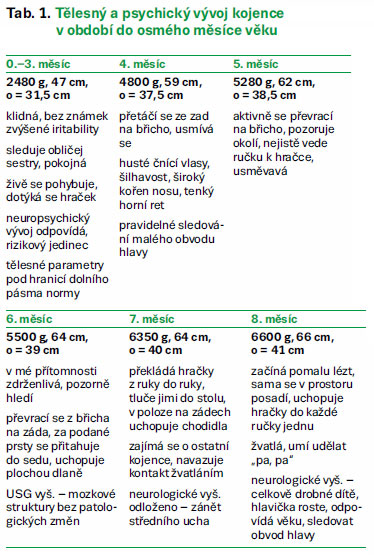

Tabulka 1 zaznamenává vývoj kojence v jednotlivých měsících života, kdy bylo prováděno vlastní pozorování. Dosavadní neuropsychický vývoj v jednotlivých měsících je neuroložkou hodnocen jako odpovídající věku kojence, doposud nebylo diagnostikováno alkoholové poškození jedince. Ačkoli jsou přítomny nízké tělesné parametry, roste kojenec progresivně.

Budoucí vývoj je těžko odhadnutelný, ačkoli je dosavadní vývoj uspokojivý, neznamená to, že tomu tak bude i nadále. Jedná se o kojence s rizikovou anamnézou a je třeba další průběžné sledování a hodnocení vývoje. Rozhodující bude nejspíš batolecí a předškolní období, kdy by se s největší pravděpodobností začaly projevovat možné psychické odchylky související s matčiným abúzem návykových látek. U jedince nemusí být diagnostikována forma alkoholového poškození, a přesto se u něj mohou vyskytovat známky svědčící pro jisté matčino užívání alkoholu v těhotenství (husté čnící vlasy, šilhavost, široký kořen nosu, tenký horní ret). Významné je tedy nyní vyhledání vhodného prostředí pro kojencův další vývoj a jeho průběžné sledování odborníky.

Jedinec byl umístěn do nejmenovaného dětského centra, kde byl prováděn i samotný výzkum. Ačkoli matka v těhotenství kouřila a pila alkohol, nebyl u novorozence diagnostikován novorozenecký abstinenční syndrom. Skutečnosti týkající se porodu hypotrofického novorozence se známkami hraniční nezralosti odpovídají údajům v odborné literatuře o nízkých porodních parametrech souvisejících s užíváním alkoholu či nikotinu v těhotenství. Králíková a Himmerová (2004, s. 271) dokonce uvádějí, že riziko malého vzrůstu stoupá s počtem vykouřených cigaret. Cigaretový kouř způsobuje vazokonstrikci, v jejímž důsledku dochází ke snížení zásobování plodu kyslíkem a živinami. Růstová retardace, vzniklá nitroděložním působením alkoholu na vyvíjejícího se jedince, je považována za jeden z charakteristických znaků alkoholového poškození (Velemínský a Žižková, 2008, s. 37). Malý obvod hlavy, který je u kojence důkladně sledován, odpovídá informacím v literatuře, které poukazují na jeho výskyt u dětí žen užívajících v těhotenství alkohol či cigarety. Ač se měsíčně zaznamenávané tělesné parametry nacházejí v dolním pásmu percentilové sítě růstové tabulky, zakreslené body znázorňují rovnoměrný růst kojence, nedochází u něj tedy k růstovému zaostávání. Dosavadní neuropsychický vývoj je ošetřující neuroložkou hodnocen jako odpovídající věku a nevyskytují se žádné psychické odchylky, o kterých se dočítáme v odborné literatuře. Kojencovu šilhavost, jež byla diagnostikována ošetřující neuroložkou, a širší kořen nosu spolu s tenkým horním rtem a hustými čnícími vlasy bychom mohli považovat za důsledek jistého alkoholového poškození. Jsou to však nespecifické známky, které mohou i nemusejí souviset s matčiným užíváním alkoholu.